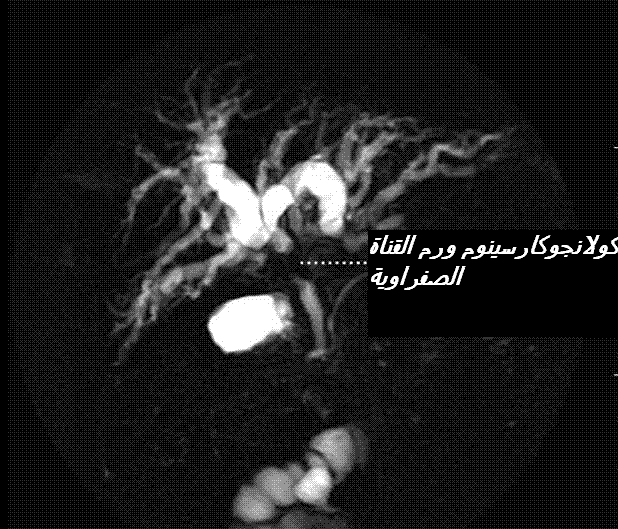

تعي حالة الكولا نجيت التقيحي (33) المصحوب بالانتكاس في البلدان الشرقية يعني نوعا شائعا لكن حالته ليست مستديمة. وتبرز الأعراض في أية مرحلة من الحياة و لكن غالبا في سن 50 .و يكتسي تردد النوبات المؤلمة صورا مختلفة و ليس استثنائيا أن يبات مجردا من الأعراض عشرات السنوات و يحتمل أن تبرز العدوى الخطيرة في شكل خراج كبدي (34) . و يمكن ان تتعرض أجزاء الكبد أين يسود الحصى ، الى نحافة (35) ناجمة عن غصن وريد بورت المناسب (36) الذي يحتك بالجزء المصاب بالعدوى .ليس استثنائيا أن تبرز الاصابة عبر تشخيص ورم الكولانجيوكارسينوم (37)

cholangiocarcinome1

الناجم عن الالتهاب المزمن للنسيج الصفراوي أو اضافة الاصابة بعدوى جرثومية . و بالرغم من عدم التأكيد ، فيبدو أن عوامل خطورة الاصابة بورم الكولانجيوكارسينوم لدى المصابين بالحصى داخل الكبد قد تبرز مؤخرة بعد مضي 10 سنوات على الأعراض كما تخلفها نحافة الكبد أو عملية الربط أي الأناس وموز الصفراوي الهضمي )38)حسب ما جاءت به بعض الدراسات الطبية . و قد يوفر التشخيص عادة بواسطة المعلومات التي يزودنا بها فحص الايكوغرافي توسيع المسالك الصفراوية داخل الكبد ( و ربما خارجه) مع وجود جزئيات لامعة داخل المنطقة الموسعة مصحوبة بظل خلفي . و يمتاز الفحص بجهاز الرنين المغنطيسي للمسالك الصفراوية و الكبد (39) بتفوق على الفحص بالسكانر .و نظرا للمضاعفات و العدوى فلا يتم اللجوء للكولان جيوغرافي المباشرة سوى قصد العلاج.

خلاصة القول : يظل الفحص المرجعي يعتمد على الفحص بجهاز الرنين المغنطيسي للمسالك الصفراوية و الكبد .